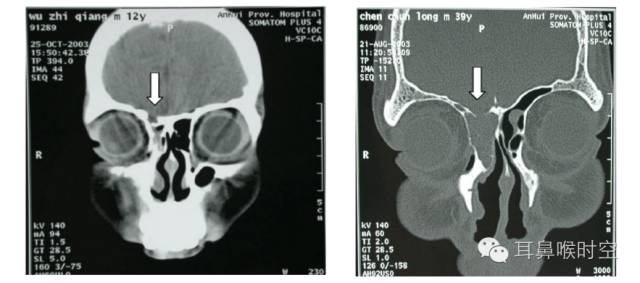

HRCT扫描

优点:良好显示颅底骨质缺损、CSF继发性征象、颅底三维重建

不受CSF漏活动性与否的限制漏口定位敏感度可达87 %~100 %

缺点:不能分辨CSF跟其他软组织

骨性裂缝不一定有CSF漏

外伤性脑脊液漏